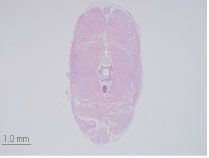

• ヘマトキシリン・エオジン染色(HE染色)標本作製

HE染色標本作製受託サービス ヘマトキシリン・エオジン染色